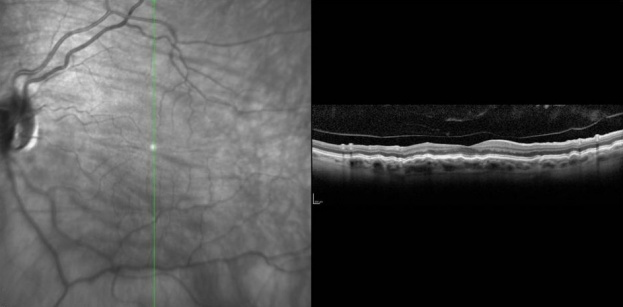

Optical coherence Tomography (OCT): Helps to confirm the diagnosis and monitor outcomes after various types of interventions. It may detect the subtle wrinkling of the chorioretinal folds in the posterior pole that may be difficult to assess with direct or indirect ophthalmoscopy. Furthermore, OCT has been shown to detect pathology in the presence of a normal ocular exam. Careful review of all radial line scans of OCT is important to assess for folds and diagnose the condition. [6]

Reference Images

- Photos Courtesy of Sarwat Salim, MD, University of Tennessee

Heidelberg OCT demonstrating chorioretinal fold with vertical scan